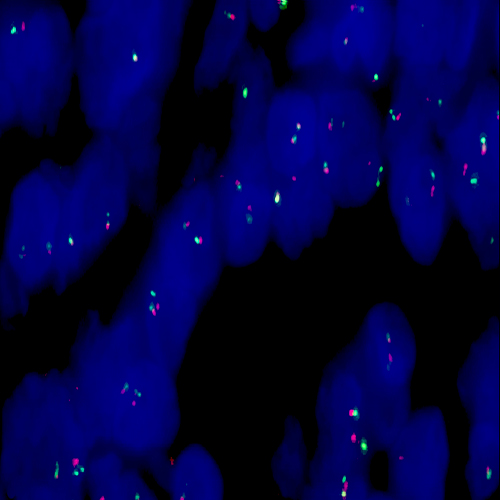

Human invasive ductal carcinoma of breast: immunohistochemical staining for AE1/AE3. Note the intense staining of malignant cells. Multi-Cytokeratin: clone AE1/AE3

Clones AE1 and AE3 are specific for the 56.5, 50, 50', 48 and 40 kD acidic cytokeratins as well as the 65 to 67, 64, 59, 58, 56 and 52 kD basic cytokeratins. The cocktail of clones AE1 and AE3 exhibit broad reactivity with two families of cytokeratin, acidic and basic.

Cytokeratin, Multi (AE1/AE3) is recommended for the detection of specific antigens of interest in normal and neoplastic tissues, as an adjunct to conventional histopathology using non-immunologic histochemical stains.